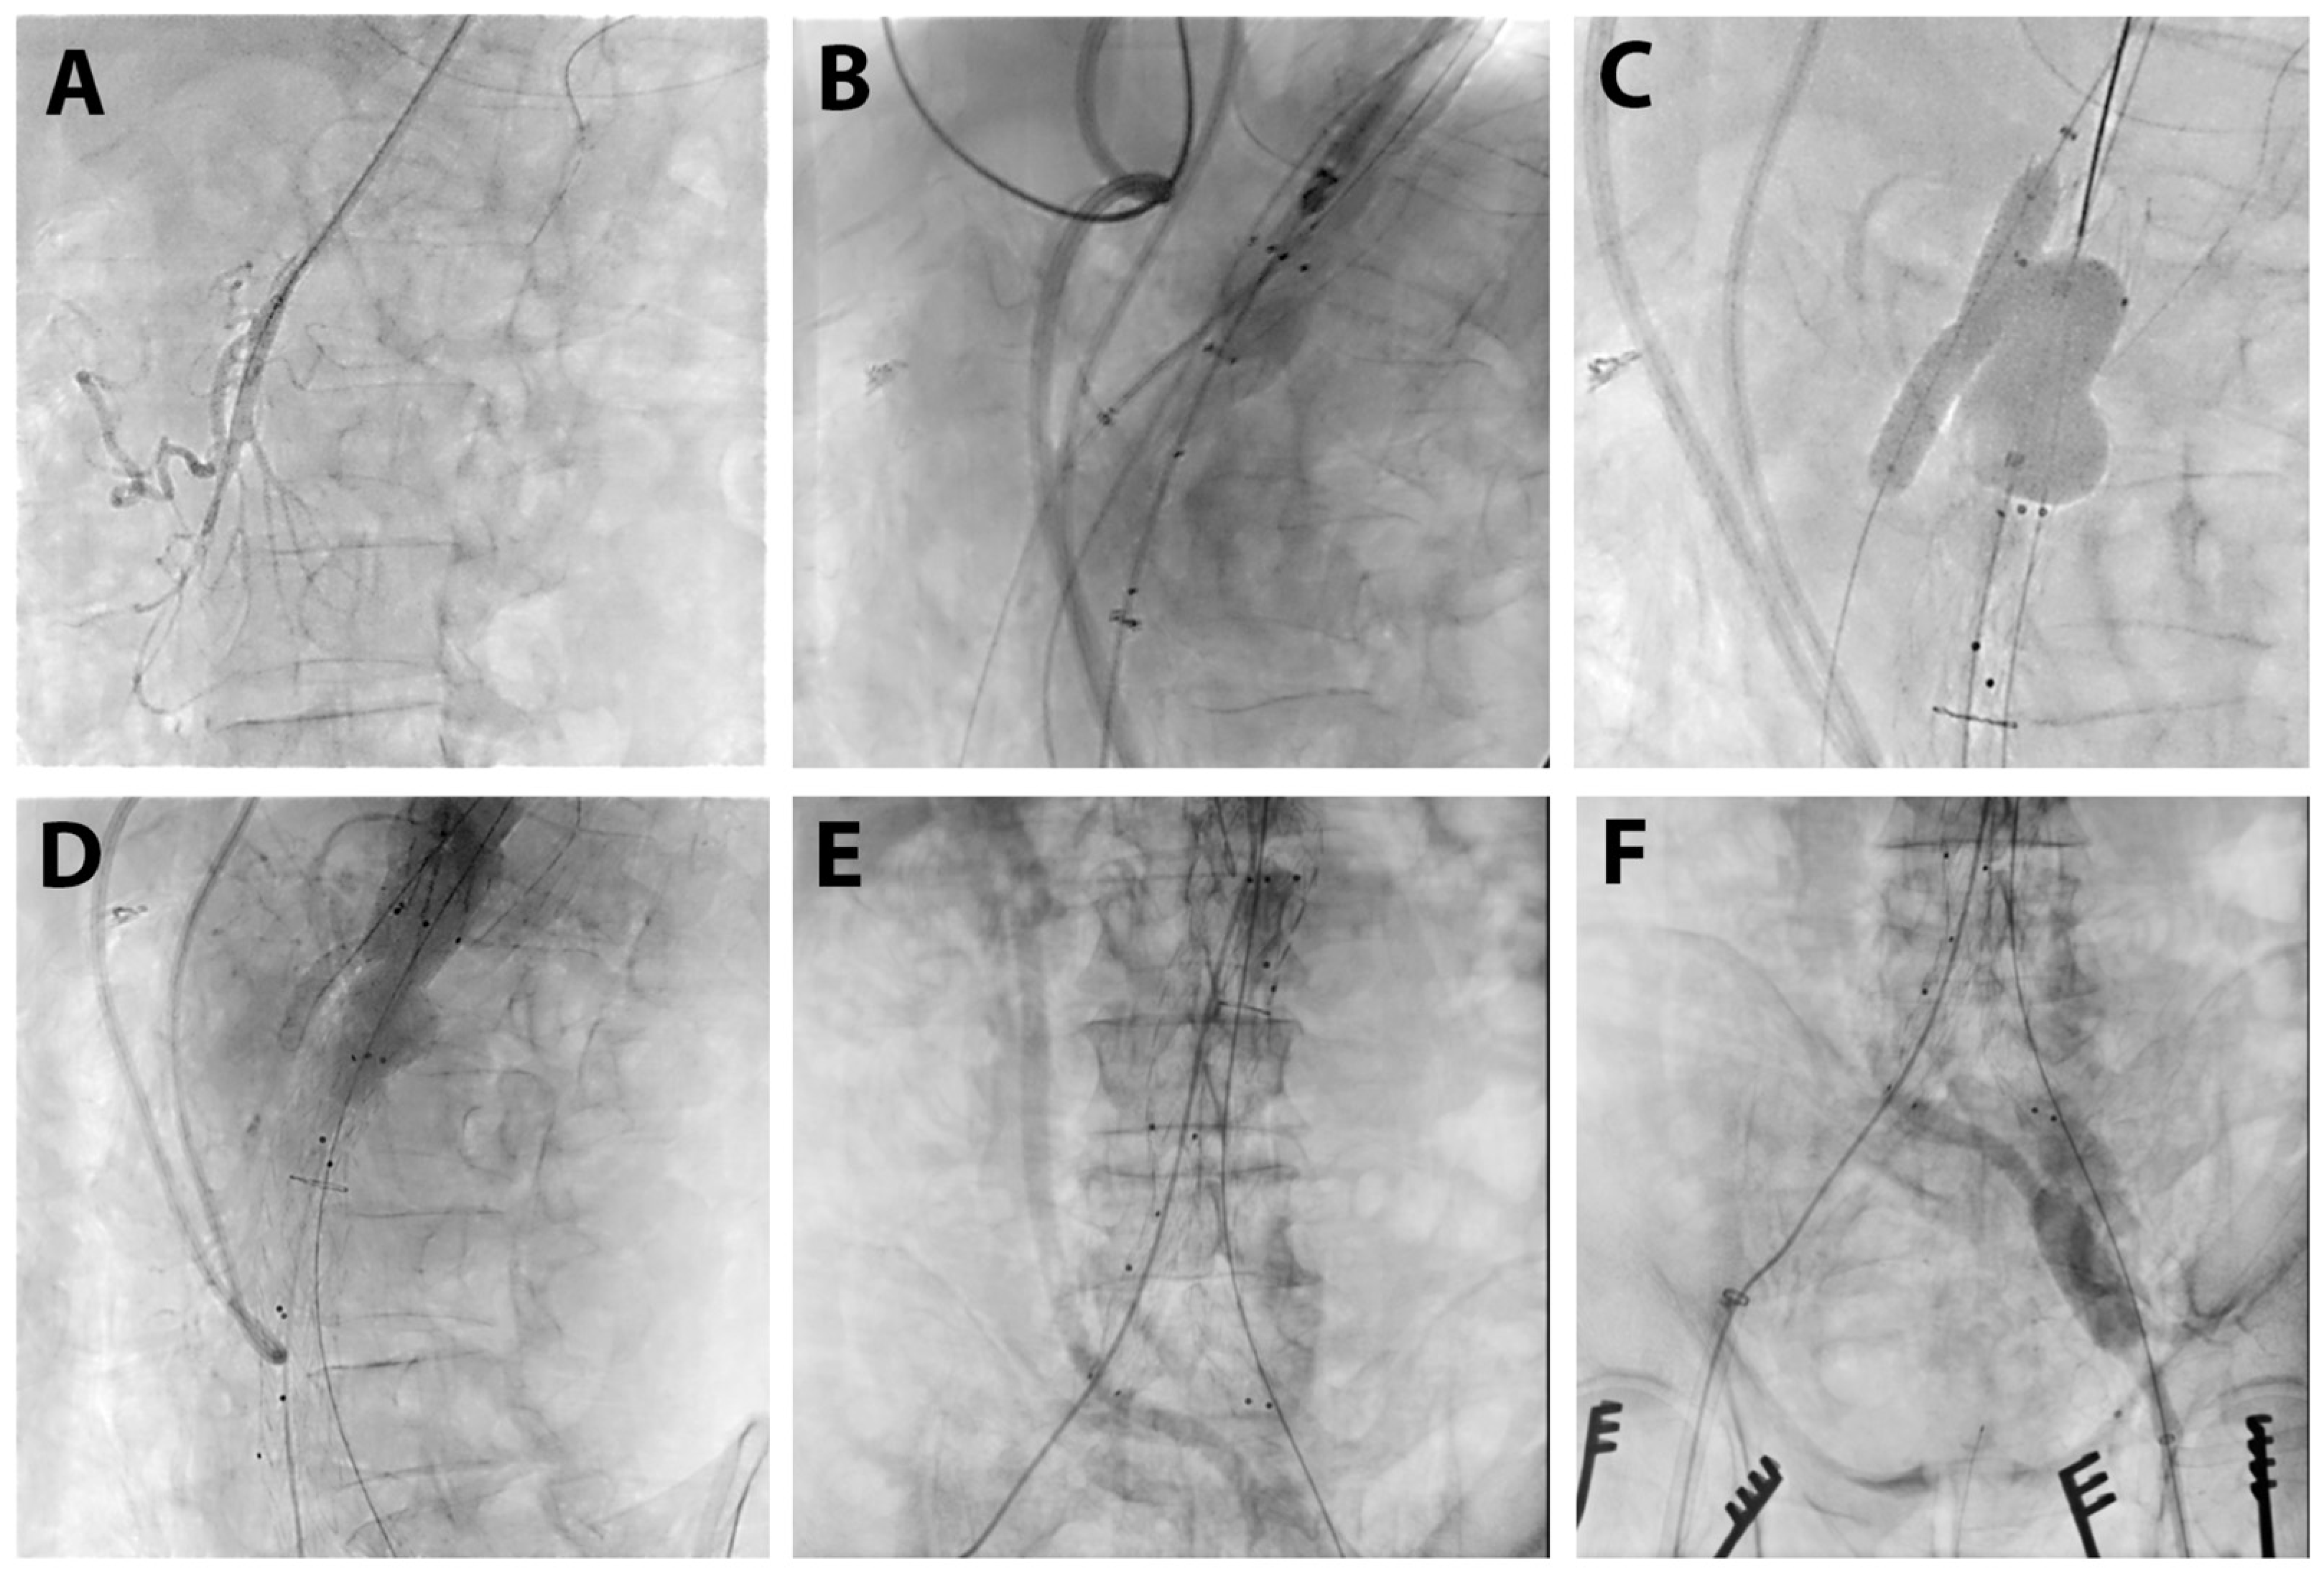

2. Case Report